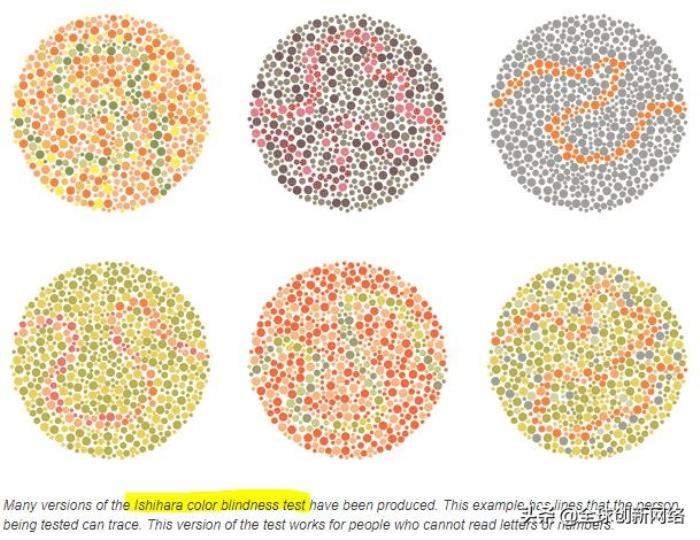

色盲测试图,看你能做对几个!

假同色图,即常见的色盲本,用不同颜色、不同深浅的色块组成一些数字、图形等,可用于色觉障碍的测试。

注:色盲本只能用来简单筛查出色觉障碍者,不能准确判断类型和程度。如果要准确诊断,则需要更专业的人员和仪器。色盲镜是诊断色盲、色弱的金标准,能判断具体类型和异常程度。

从简单到困难,你能做对几个?

·数字图1

结果:正常看到的是66,看不出是红绿色盲

·数字图2

结果:正常看到的是698

·数字图3

结果:正常看到的是6,看不出是绿色盲

·数字图4

结果:正常看到的是29

·数字图5

结果:正常看到的是812

·数字图6

结果:正常看到的是628